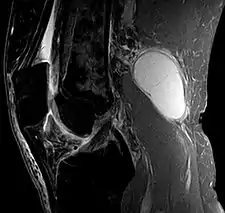

Baker's cyst on axial MRI with communicating channel between the semimembranosus muscle and the medial head of the gastrocnemius muscle. Baker's cyst on MRI, sagittal image

Baker's cyst on MRI, sagittal image Baker's cyst on MRI, sagittal image

Baker's cyst on MRI, sagittal image